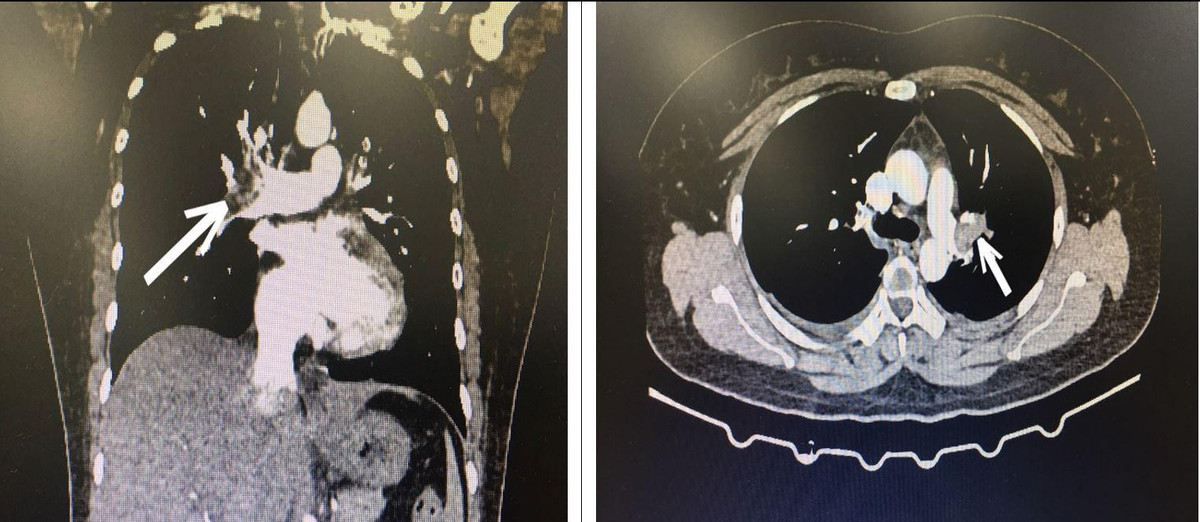

Bác sĩ cấp cứu hướng chẩn đoán tới bệnh thuyên tắc động mạch phổi cấp và quyết định cho chụp CT ngực có tiêm thuốc cản quang, kết quả là hình ảnh huyết khối động mạch phổi 2 bên.

Hình ảnh CT lồng ngực bệnh nhân bị tắc động mạch phổi cấp tính.